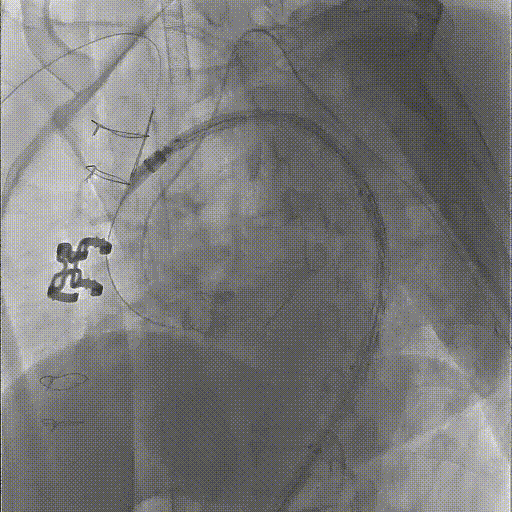

★ Case 2

男性,50岁,胸痛7+小时;

既往史:既往诊断高血压,未规律服药及监测血压;

个人史:吸烟30余年,日均20支;

夹层动脉瘤CTA:A型主动脉夹层,初破口位于主动脉弓近端,逆撕至主动脉根部,左颈总动脉及左锁骨下动脉根部受累,夹层远端累及至双侧髂动脉。

置入双分支术中支架